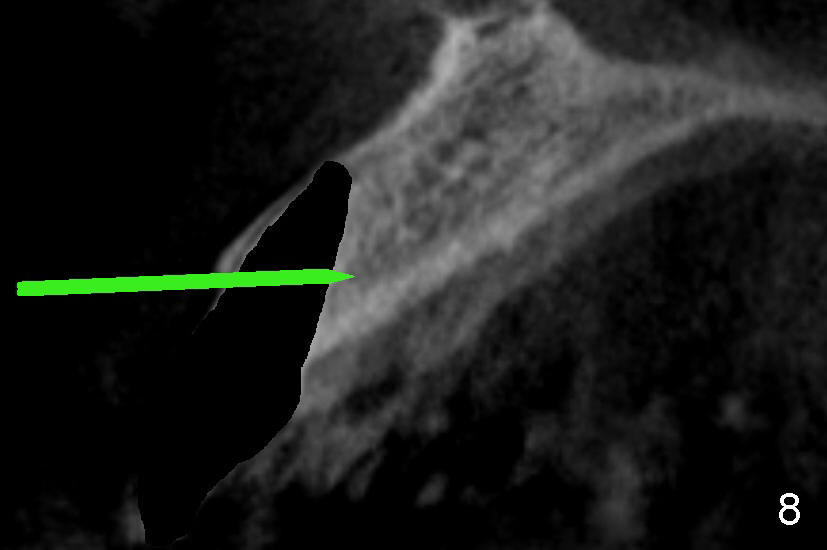

四十四岁女病人上颌中切牙突然断裂(图一:8),经过讨论,她同意植牙。由于根尖(图二黑线轮廓)上方骨头很多(箭头:鼻底),适合立刻植牙。牙根长度十一毫米左右,宽度约五毫米,准备植入直径五毫米植牙。拔牙后使用两毫米钻头,深度二十毫米(图三从颊侧牙龈缘算起),超过牙槽窝底部接近七毫米,所以植牙至少有七毫米新骨支持,将非常稳定。然后逐步使用2.5, 3.0, 和3.5毫米钻头,同一个深度,边钻边注意钻头(图四:D)近远中(图四)以及颊舌侧(图五)方向。